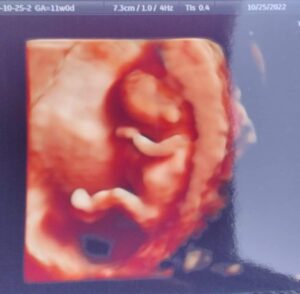

Tubal Clip Reversal, Baby Taylor Due May 2023

11 Weeks Along!

This is Baby Taylor at 11 weeks. This is the final addition to the family! Due May 2023!

Patient age: 37

Tubal ligation type: Tubal clips (clamps)

Patient hometown: Inwood, West Virginia